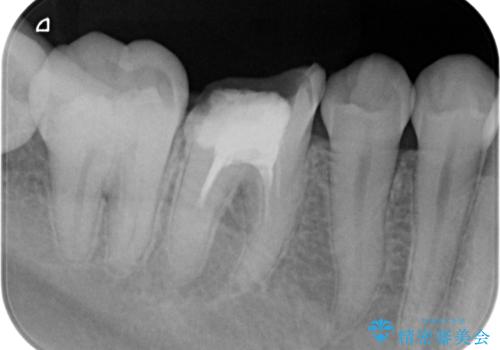

過去に根管治療がされている歯でしたが、現在症状はなく、レントゲンでも根尖病巣がないが根尖まで薬が到達していない状態でした。

そのまま被せ物だけやりかえるか根尖病巣の再発のリスクを考えて再根管治療を行うか患者様に決めて頂きました。